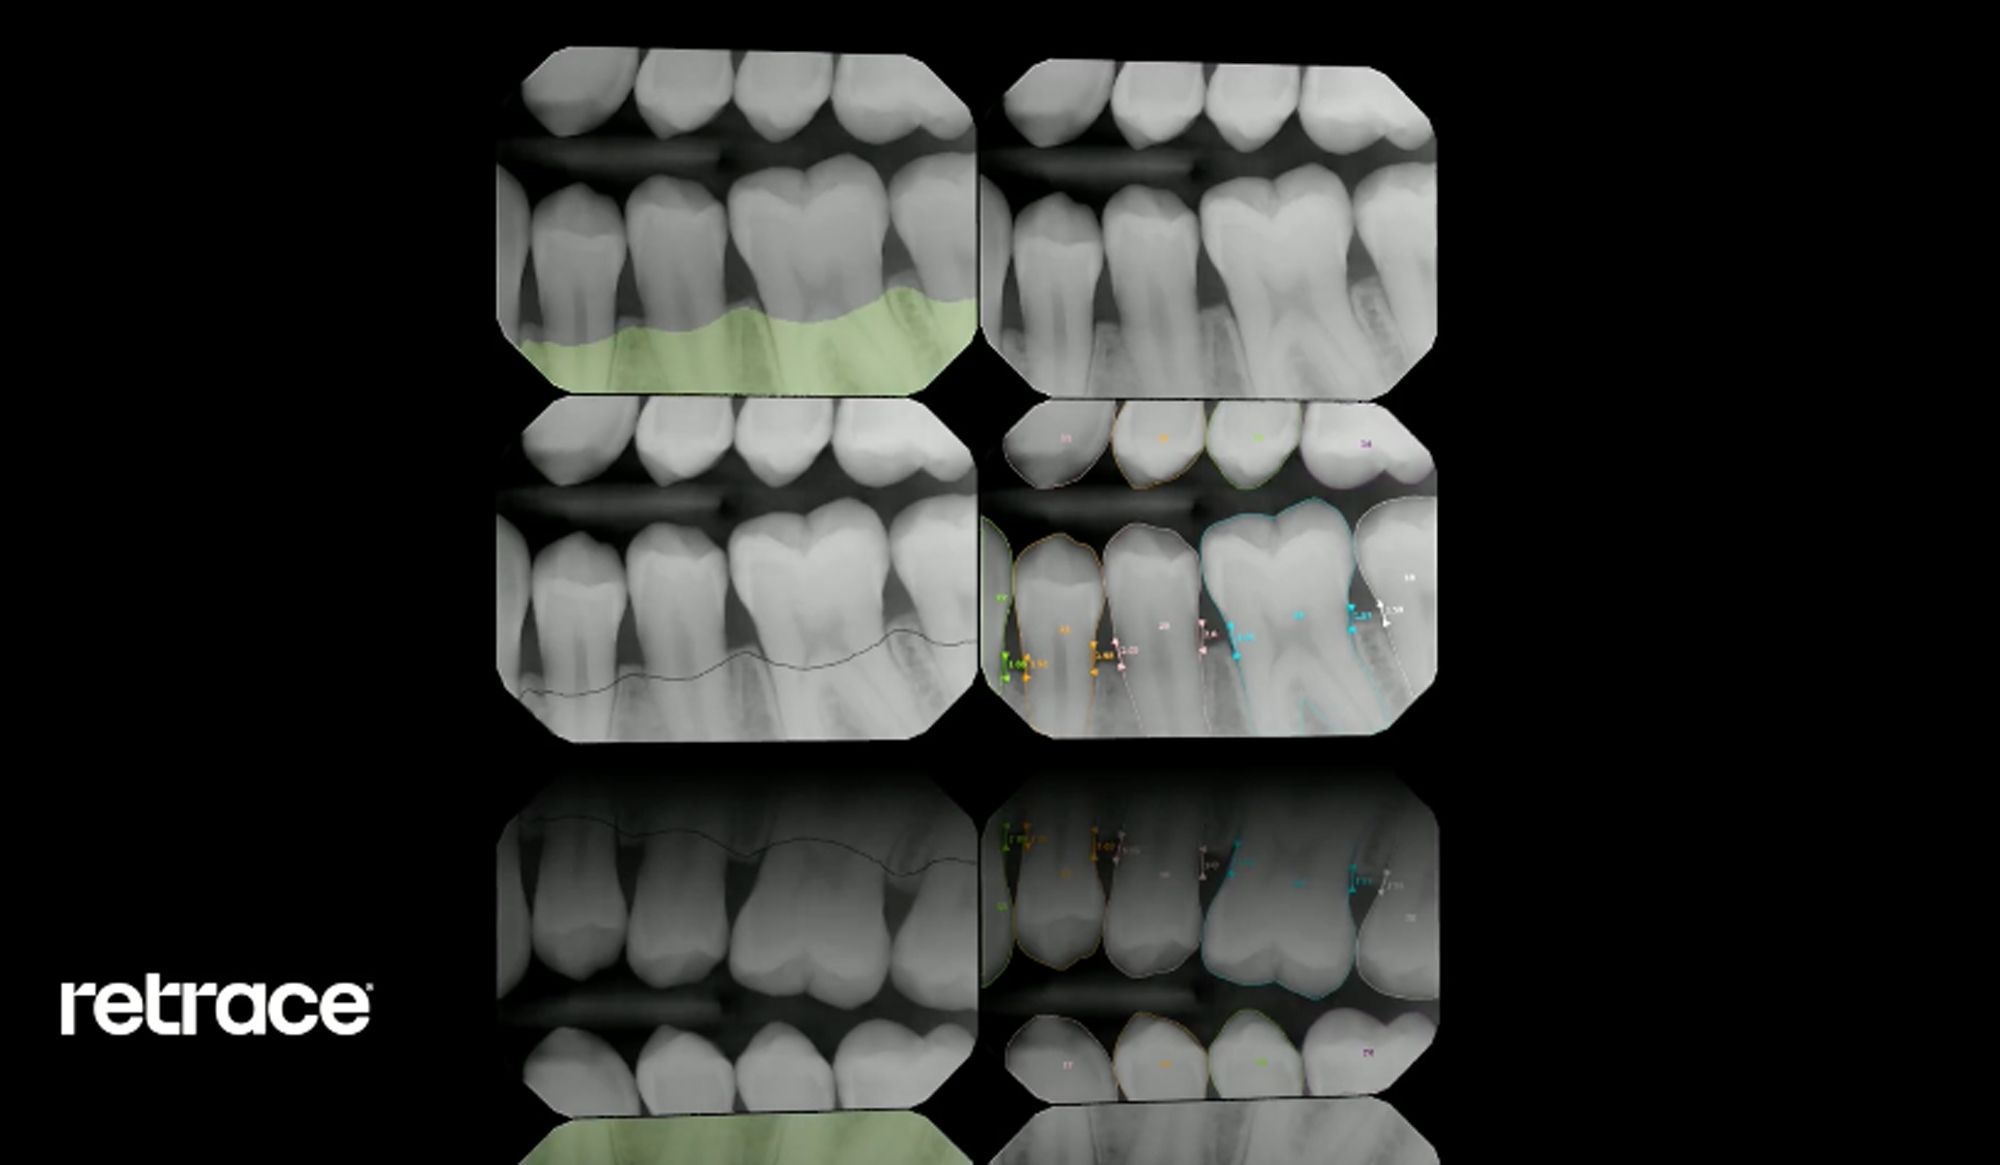

Dental artificial intelligence group Retrace has announced the publication of a new study called “A generative adversarial inpainting network to enhance prediction of periodontal clinical attachment level.” This study examines the use of “Deep Fake” technology for the improvement of diagnostic accuracy of artificial intelligence (AI) algorithms in identifying periodontal disease.

With standard dental radiographs, errors can present in image distortions or patient anatomy. The study took a look at 10, 687 radiographs with independent validation from clinicians and researchers, and eventually demonstrated that a generative adversarial network or “Deep Fake,” improved AI accuracy in periodontal disease detection.